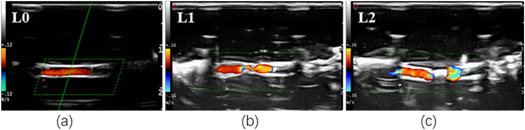

Color Doppler flow imaging (CDFI): CDFI function of probe was used to observe occlusion after vascular sonication. Figure 3 shows the results of the sonicated vessel evaluated by the combination of B-mode imaging and CDFI. The changes of vascular mimic tubes were graded as three, L0, L1 and L2 (see table 5).

Figure 3. The occlusion level of ex vivo vessels in CDFI.

Standard image High-resolution imageTable 5. Grading of vascular occlusion levels described by B mode imaging and CDFI.

| Occlusion level | B mode imaging | CDFI |

|---|---|---|

| L0: not occluded | Obvious gap | Continuous color flow signal |

| L1: partial occlusion | Narrow gap | Thinner color flow signal |

| L2: complete occlusion | Obvious highlighted | Obvious breakpoint |